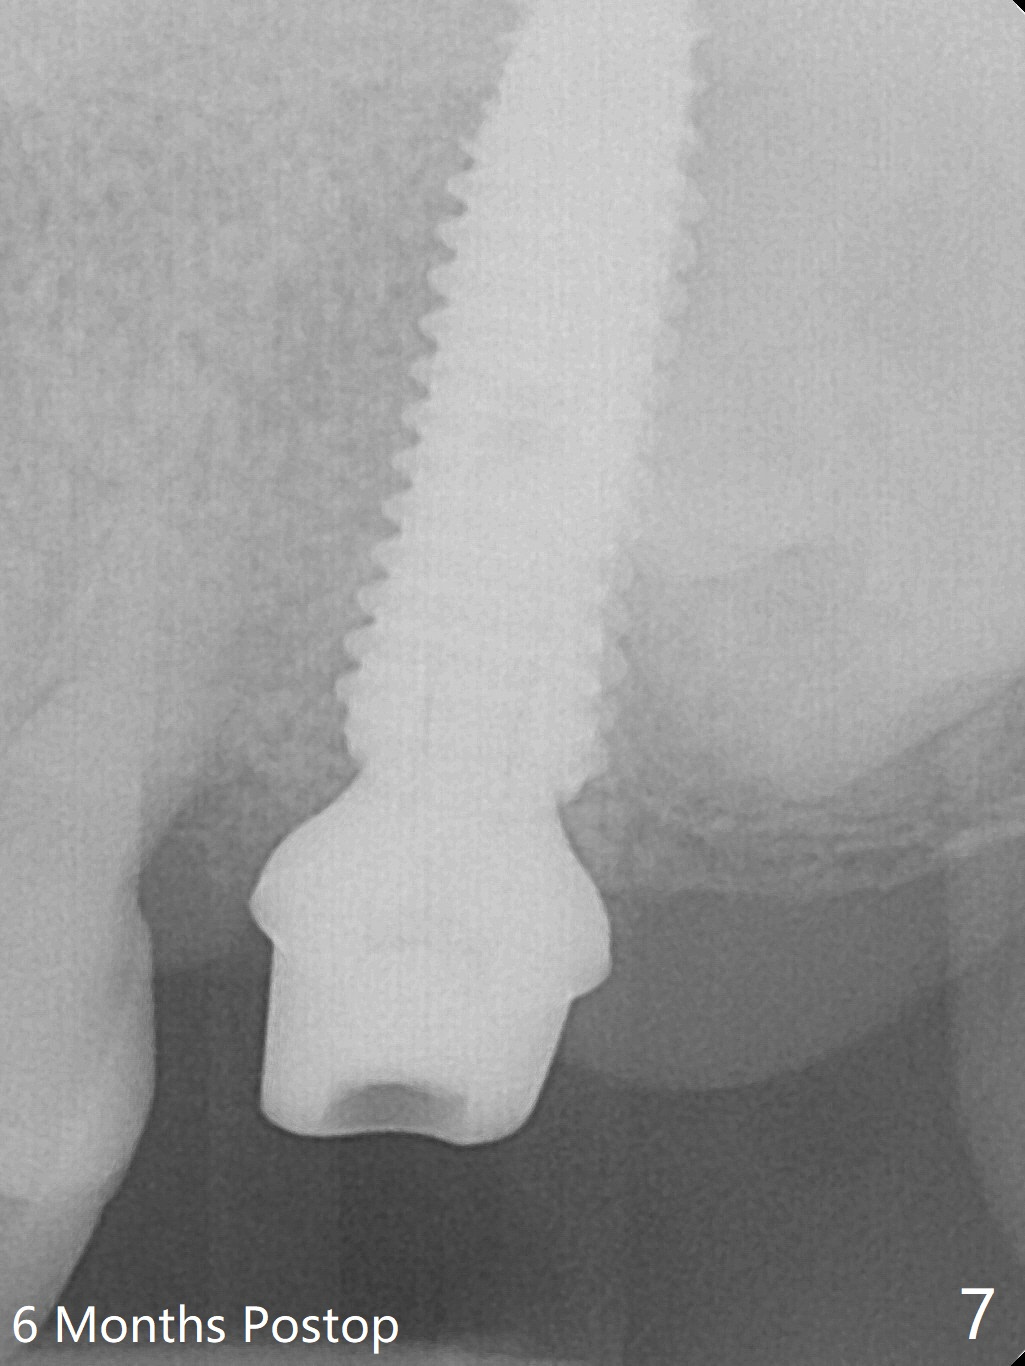

Extraction of the tooth #15 with short clinical crown (suggesting bruxism, Fig.1) reveals a vertical root fracture (Fig.2 <). It seems unnecessary and difficult to create osteotomy in the mesial slope. What can be done is to place starter and 2 mm drills as mesial as possible (Fig.3 (red dashed line: sinus floor). After use of Lindamann bur to move the osteotomy mesially and sequential osteotomy until 3.8x18 mm, a 4.5 mm tap is inserted with clearance from the impacted tooth #16 (Fig.4). A 5x15 mm implant is placed with >60 Ncm with clearance from the 3rd molar (Fig.5,6). If the impacted tooth were removed, the primary stability is expected to be reduced. Impression is taken 6 months postop with 19/20 implants (Fig.7). The bone graft remains in the crestal area immediately and 11 months post cementation (Fig.8,9 *). In the other word, new crestal bone forms after extraction.